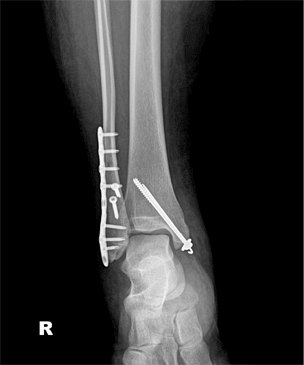

발목관절 골절의 치료

x-ray 사진

발목 골절 수술 후